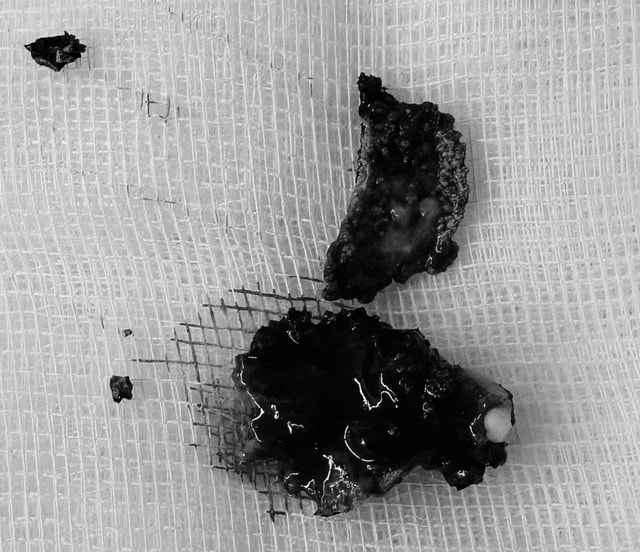

Để điều trị dứt điểm cho bệnh nhân, các bác sĩ tiến hành phẫu thuật nội soi, lấy dị vật có kích thước khoảng 2 cm ra ngoài. Sau đó, bệnh nhân được chỉnh hình vách ngăn mũi, giúp đường thở thông thoáng hơn.